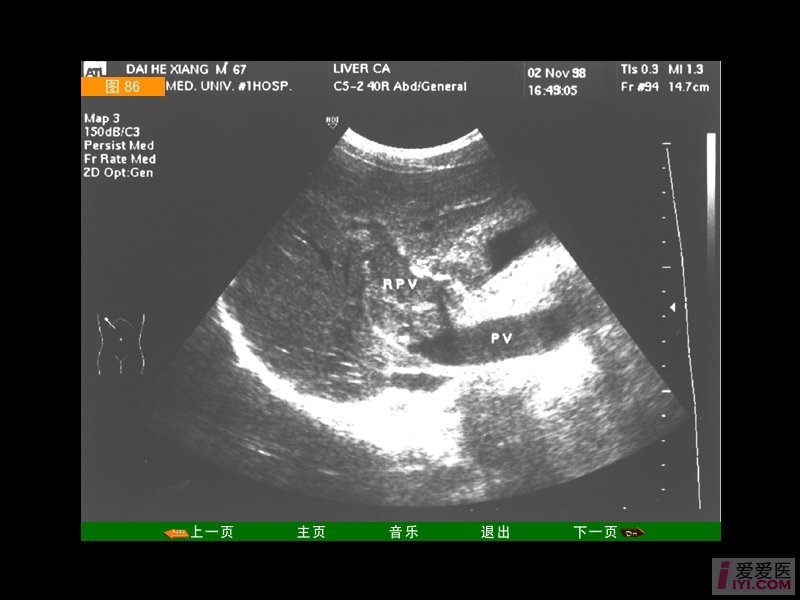

肝功,肾功,电解质,肿瘤标志物,血糖等指标均正常;心电图正常;腹部b超

图片尺寸3968x2976